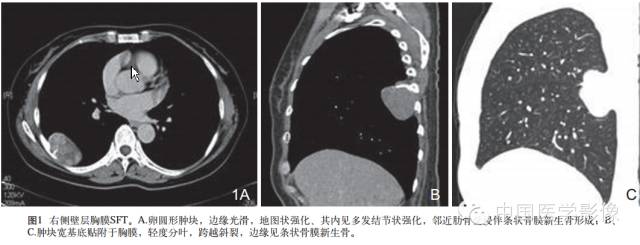

1.外形及囊变坏死:良性SFT一般为边界清晰的单发肿块无分叶或浅分叶,肿瘤大多呈实性,囊变坏死区较小。恶性SFT一般为囊实性或囊性为主肿块呈分叶状坏死范围广泛。

2.密度或信号特点:肿瘤实性部分CT表现为软组织密度,囊变坏死区呈低密度。位于胸腔的SFT尽管体积巨大,但密度相对均匀,坏死少见且范围多较小。良性肿瘤坏死少见,恶性肿瘤不规则坏死区相对多见。腹部SFT都有不同程度的坏死囊变和钙化。MRI除了能够提供明确肿瘤的确切部位及累及范围外,对于明确肿瘤的组成成分具有重要价值。MR信号改变与肿瘤的组织学特征密切相关,其内成熟的纤维组织在T1WIT2WI序列上均呈低信号,而肿瘤细胞及血管聚集区则呈等T1长T2信号,因此T1WI一般为等信号或低信号T2WI多为混杂信号。文献认为T2WI低信号对于本病诊断具有重要价值。

3.包膜:良性孤立性纤维性肿瘤多具有明显的包膜,文献报道包膜出现率约50%。包膜出现可能与肿瘤缓慢生长过程中对周围正常组织缓慢压迫有关。

4.铸型生长:由于良性SFT生长缓慢,发生于胸膜腔的孤立性纤维性肿瘤常呈斜圆锥体状,铸型镶嵌于肋膈角。此征象的出现与病灶生长时间及部位密切相关。

6.增强扫描:SFT为富血供肿瘤,增强扫描呈肿瘤实性部分呈地图样明显强化、延迟扫描进一步强化是SFT的主要特征。病灶实性部分显著强化与镜下血管外皮瘤样分布区及细胞密集区有关,而肿瘤内部坏死囊变区不强化。此外,细胞稀疏区与胶原纤维束玻璃样变区域强化相对较弱,因此形成地图样不均匀强化表现。持续性强化的模式可能与病灶内胶原纤维缓慢强化有关,还可能与黏液样变及细胞疏松排列导致细胞外间隙扩大对比剂在细胞外间隙内进行性聚集有关,因此动态扫描对于本病的诊断具有重要价值。

7.肿瘤继发性改变:胸腔积液,邻近肺组织受压移位、不张,呈“帽状”实变。可伴有周边骨质破坏及溶骨改变。